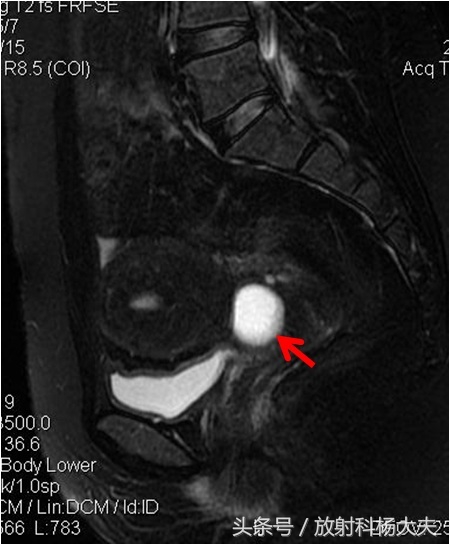

宫颈囊肿又叫宫颈纳氏囊肿,宫颈纳氏囊肿(可称“那囊”也有叫纳囊的)同宫颈糜烂、宫颈息肉一样,是慢性宫颈炎的一种表现。宫颈长3厘米左右,上端与子宫相连,下端在阴道的最深处。宫颈表面有腺体,可以分泌粘液。当子宫颈受到损伤或者发生炎症时,在修复的过程中,腺体的开口被新生的上皮组织堵塞,分泌的粘液不能顺利地流出来,就形成了所谓的“囊肿”!在核磁上,这种囊肿因为含水丰富,在T2WI上呈白白的高信号,里面信号很均匀,做了增强扫描,也不会发现里面有异常强化。当然,也可以分辨是否合并感染。周围有无肿瘤等等。

但在核磁上,准确诊断宫颈纳囊是第一步。因为还有一些非常少见的情况需要与宫颈囊肿区分,比如子宫内膜异位症发生在宫颈时也可表现为囊,但跟纳囊比较,其信号往往复杂,而且掺杂出血,容易鉴别。